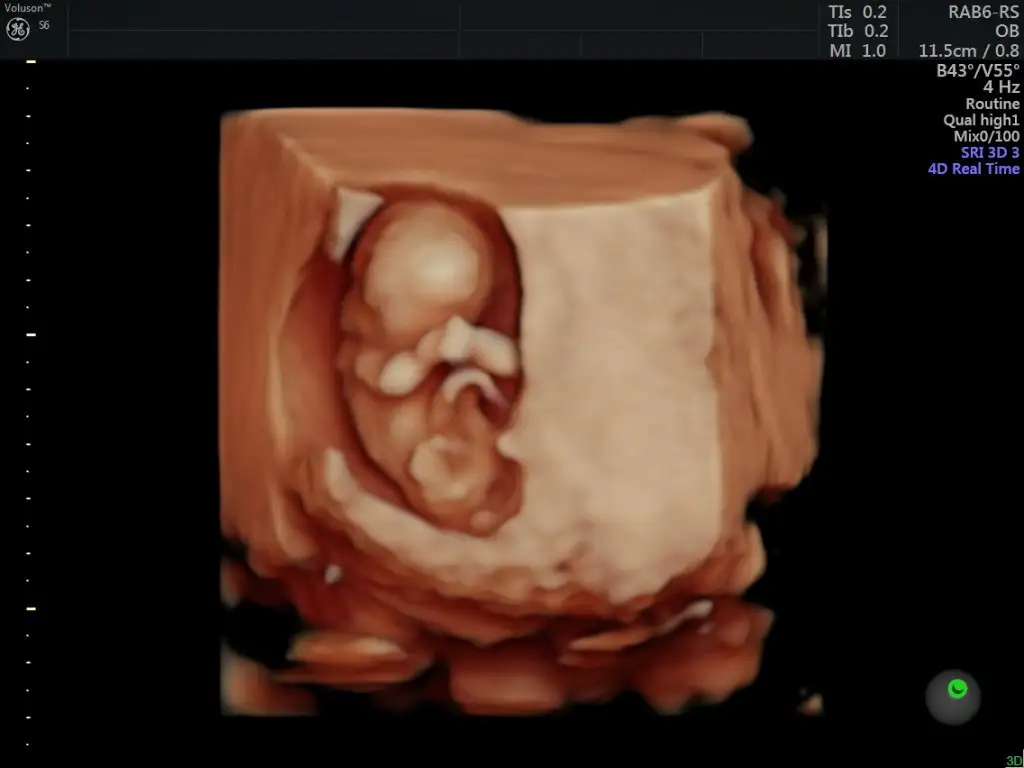

Bugün öğrendik,kızmış cinsiyetimiiiz :Maşallah Allah hayırlısıyla kucağınıza almayı nasip eylesin inşallah

Siz anlıyorsunuz galiba banada yorum yapabilir mısınız bugün doktora gittim 12 haftalık ama küçük daha zamanı var dedi Meraktan catliyorumCanım erkek gibi

Canım kız gibi11+2 karından ultrason cinsiyet yorumu yapabilir mısınız ?